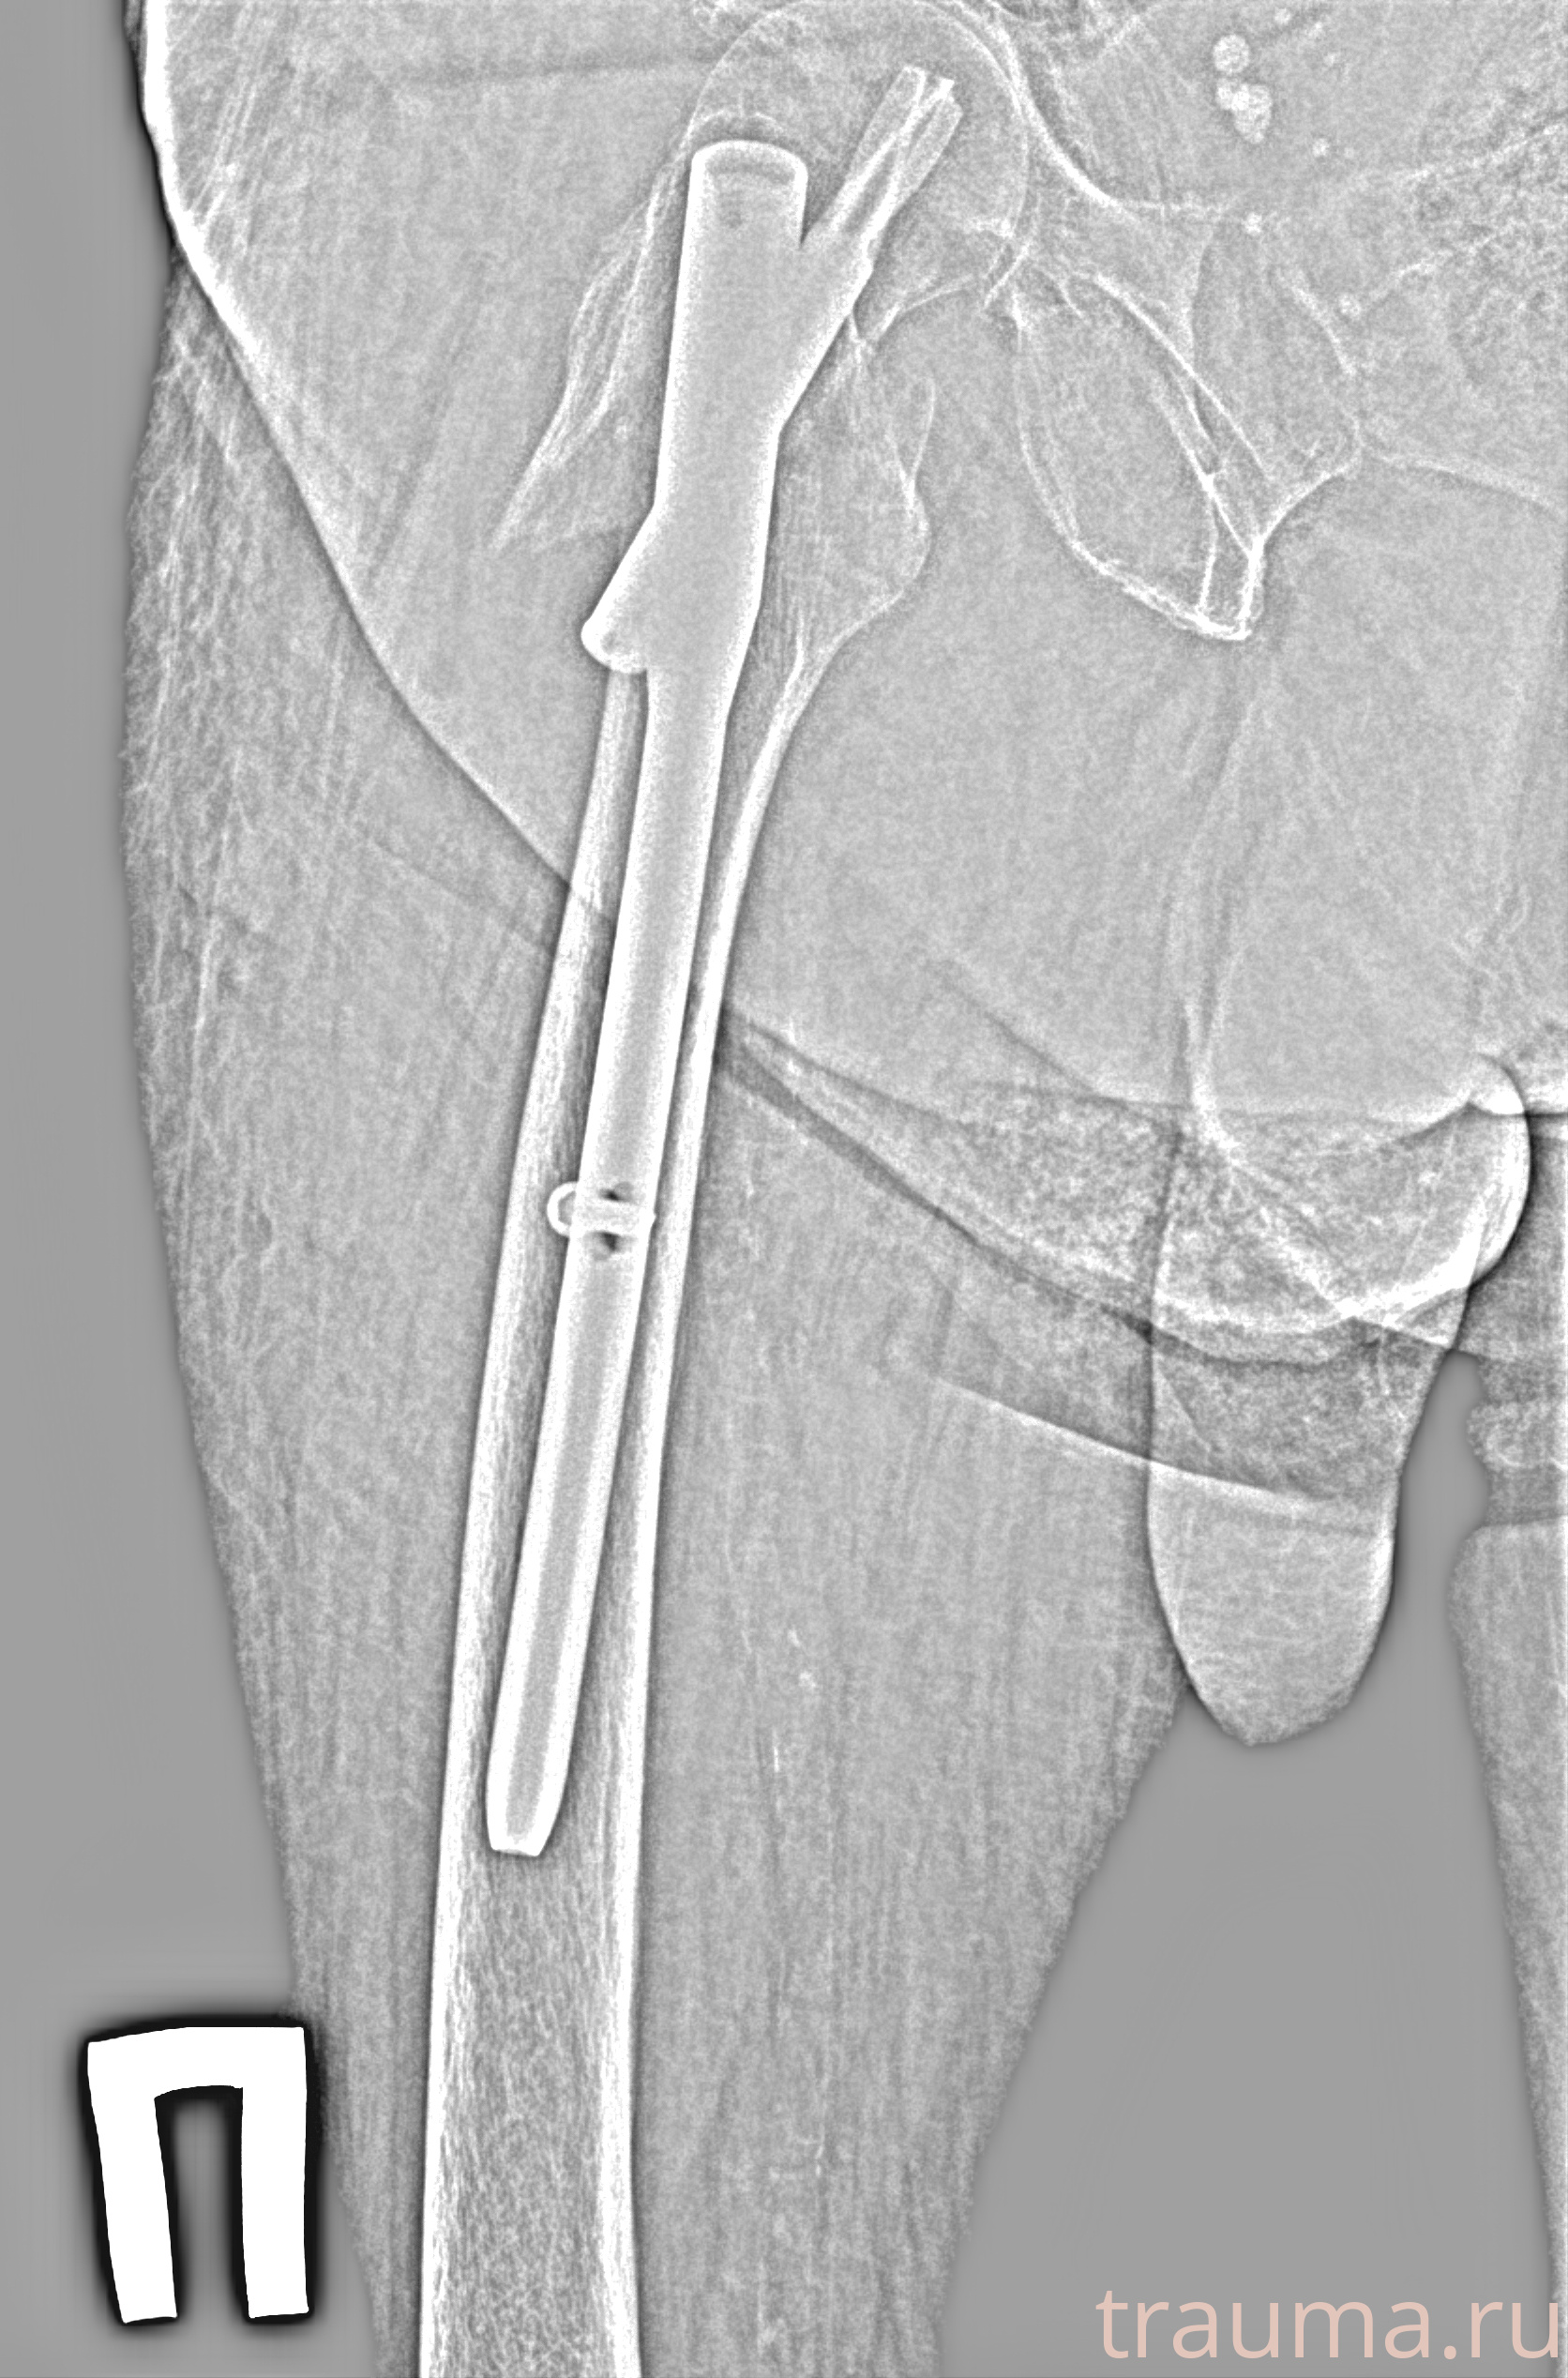

Рентген на дому: по вашему адресу приезжает врач-рентгенолог, травматолог-ортопед с мобильным рентгеновским аппаратом, проводит диагностику травмы или заболевания, делает необходимые рентгенограммы, дает рекомендации по дальнейшему лечению. Получить качественные снимки в домашних условиях возможно благодаря уникальной методике, разработанной МосРентген Центром для института  Склифосовского